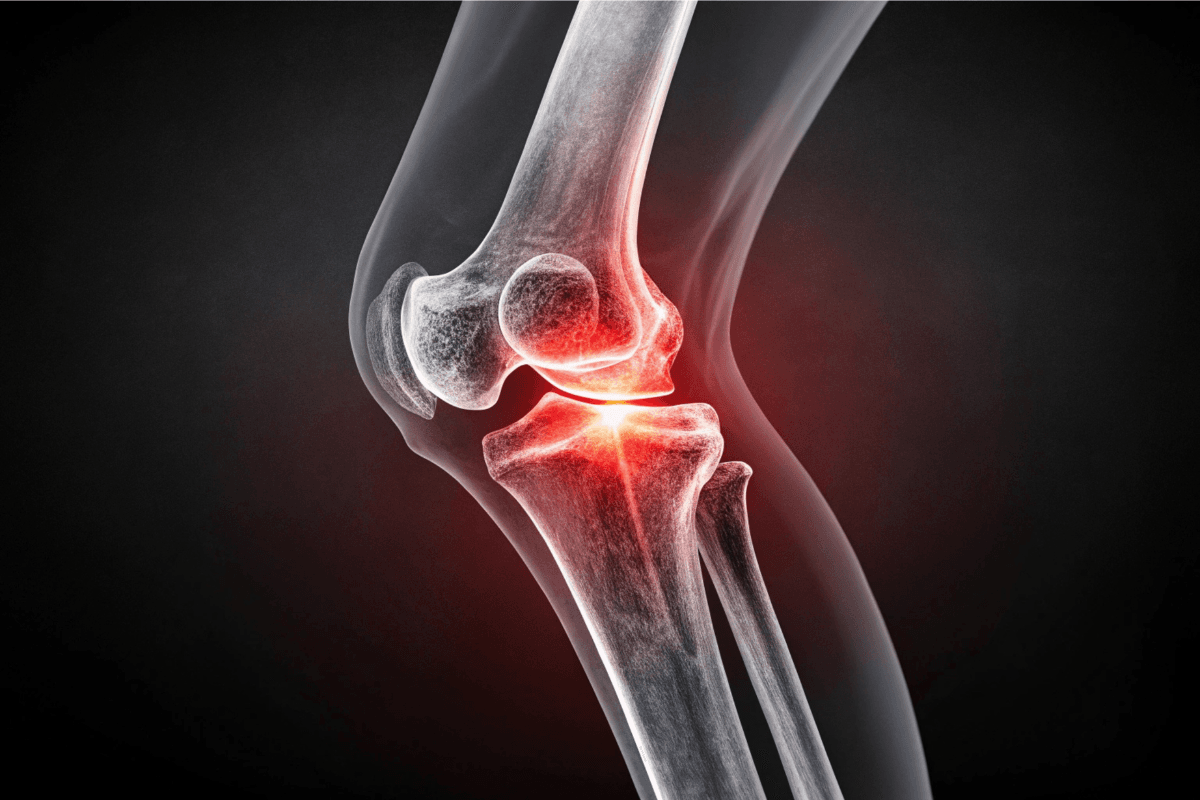

Knee Ligament Repair

ACL, PCL, and MCL injuries are repaired using minimally invasive arthroscopic methods, ensuring strong, flexible, and pain-free joint recovery.